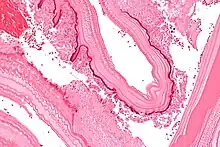

Larval/hydatid cyst stage

From the embryo released from an egg develops a hydatid cyst, which grows to about 5–10 cm within the first year and is able to survive within organs for years.[25] Cysts sometimes grow to be so large that by the end of several years or even decades, they can contain several liters of fluid. Once a cyst has reached a diameter of 1 cm, its wall differentiates into a thick outer, non-cellular membrane, which covers the thin germinal epithelium. From this epithelium, cells begin to grow within the cyst. These cells then become vacuolated, and are known as brood capsules, which are the parts of the parasite from which protoscolices bud. Often, daughter cysts also form within cysts.[24]